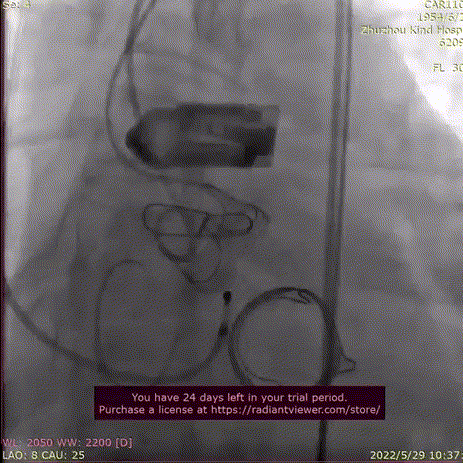

主动脉根部造影,主动脉瓣生物瓣中大量反流,直头导丝顺利跨瓣。

主动脉根部造影

导丝跨瓣